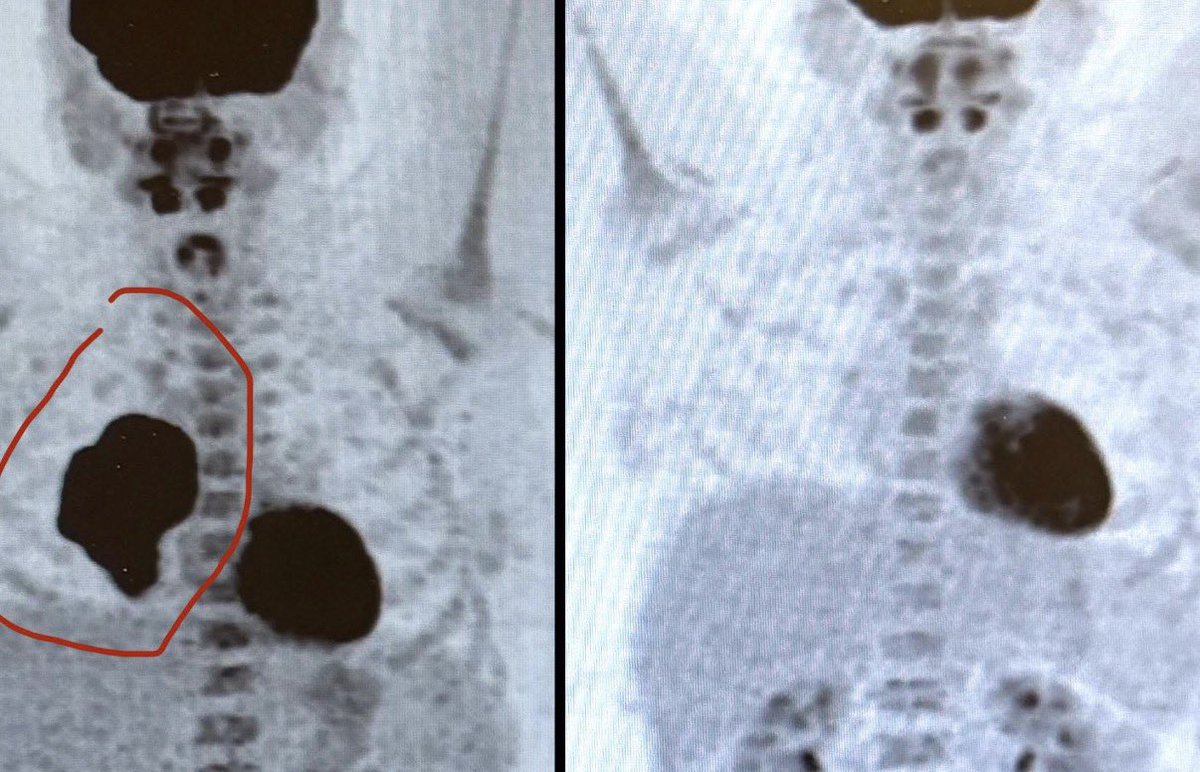

@obenson34 Holy crap! It’s huge! 12 treatments is alot though. My grandpa had the same & recovery was horrible. Hope ur recovering well an fast

@_awkwardlezbean Yeah it was crazy to see the before and after. It was bigger than my heart. It was in the center but pressing on my heart and lung. Only needed 12 chemo treatments & it was gone. I had Hodgkins Lymphoma. It’s very treatable unlike non-Hodgkins.

I was really fortunate